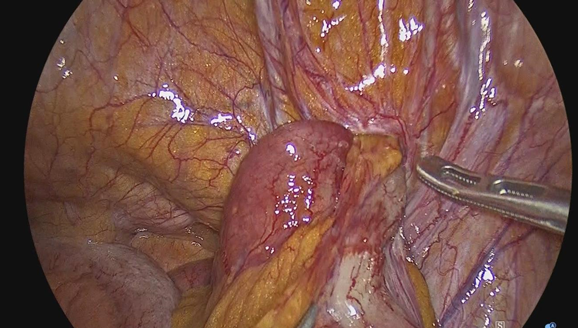

A 93-year-old woman presented to the emergency department with a 1-day history of right lower quadrant abdominal pain that moved into the right groin area. On physical examination, presented with left lower quadrant pain, decreased peristaltic sounds and abdominal distension. Laboratory data demonstrated leukocytosis. Abdominal computed tomography showed an incarcerated right femoral hernia of the appendix with dilatation of the appendix (Figure 1 & 2). She underwent laparoscopic surgery where an incarcerated colon was observed in the internal ring of the right femoral canal (Figure 3 & 4). Appendectomy was performed after reduction (Figure 5). The right femoral hernia of the internal ring was closed with a primary suture (Figure 6 & 7). Pathologic anatomy revealed appendicitis with reactive lymphoid aggregates. From the beginning he was treated with antibiotics, and adequate parenteral fluid management. The postoperative period was adequate, she did not present abdominal symptoms such as pain or nausea. She was discharged 4 days after a successful appendectomy and hernia repair.

Figure 3 Colon is observed in femoral hernia without macroscopic data of intestinal ischemia or peritonitis.

Figure 4 Colon traction gently performed.